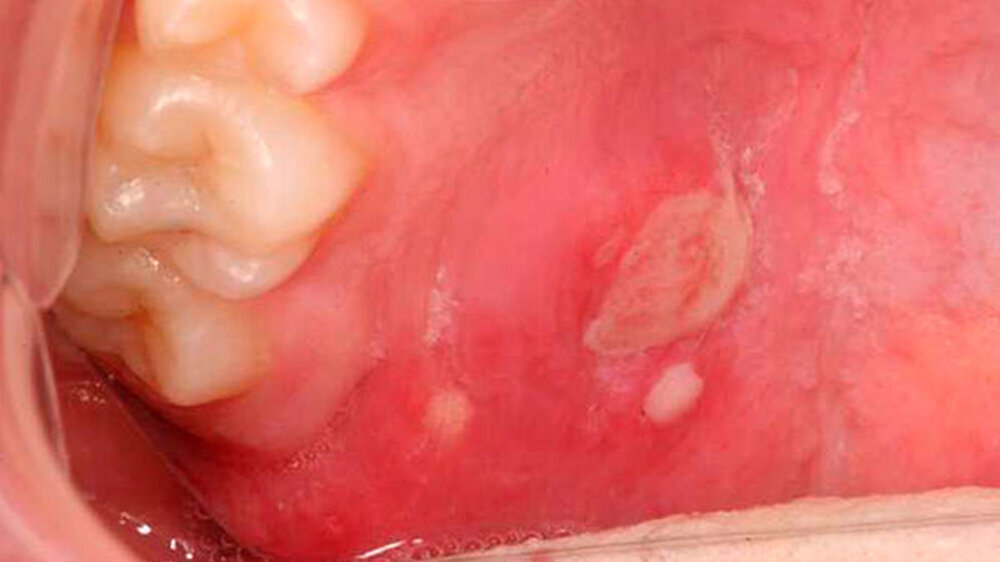

Orale Aphthen und aphthoide Läsionen

Differenzialdiagnosen der Aphthen sind Malignome und deren Vorstufen, andere Stomatopathien, reaktive Veränderungen der Mund- und Rachenschleimhaut, gastrointestinale Syndrome, mukokutane Erkrankungen des rheumatischen Formenkreises, bullöse und lichenoide Dermatosen und Infektionskrankheiten. Sie alle können sich mit Mundaphthen präsentieren.

Eine Aphthe, deren symptomatische Schmerzbehandlung nicht in etwa zwei Wochen zum Erfolg führt oder zumindest eine Rückbildungstendenz zeigt, muss unbedingt zur weiteren Diagnostik (histologische Abklärung) an die Fachabteilung überführt werden.